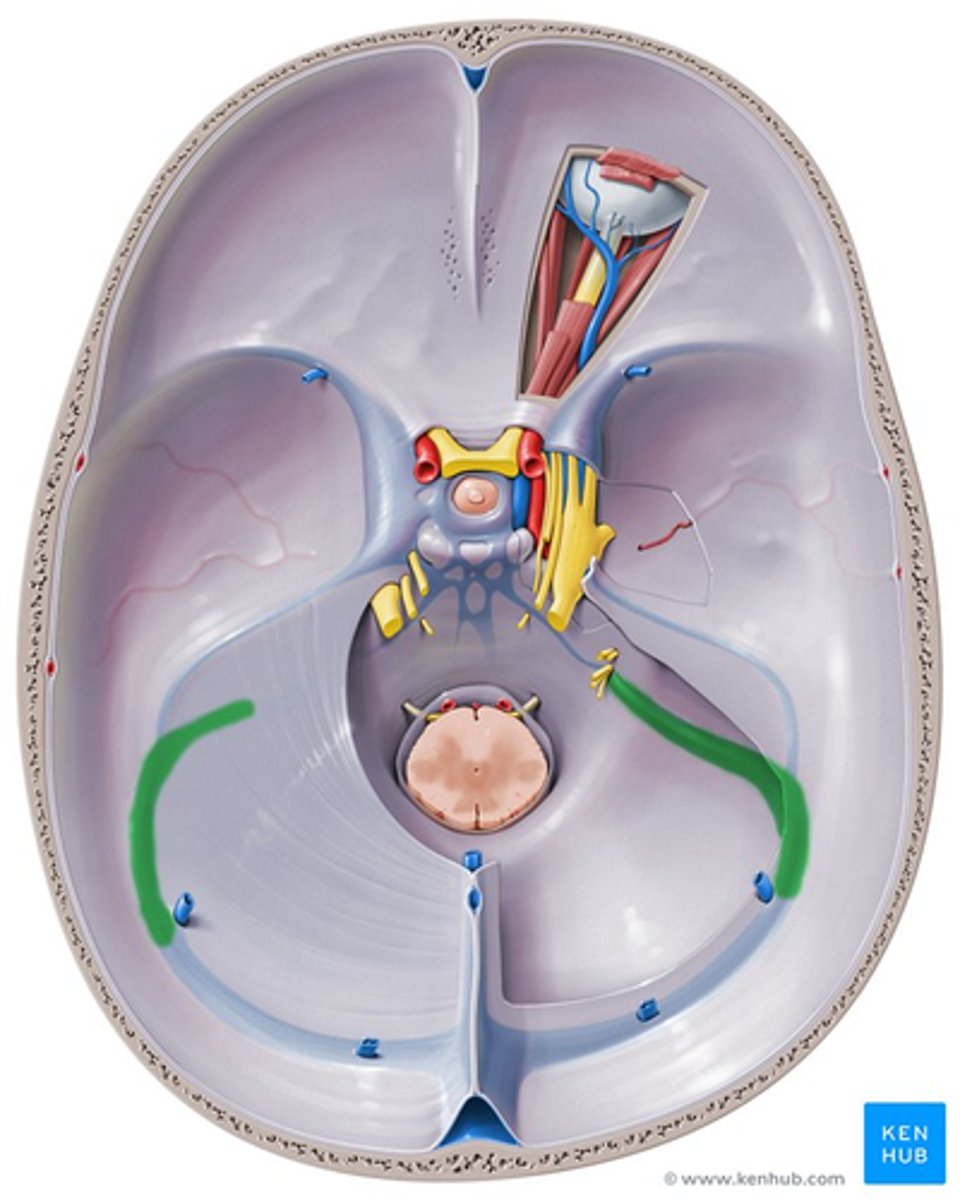

sigmoid sinus

trigeminal ganglion